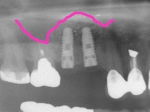

ショートインプラント

術前術前骨の高さが不足している場合、通常のインプラントでは処置が不可能なものが多い。特殊なショートインプラントを用いて可能になる例。 術前 術前CT像術前CT像術前CT像、下歯槽神経が下あごの中央部を走行しているため利用できる骨の高さが少ない。 埋入予定計画埋入予定計画埋入予定計画 術後レントゲン術後レントゲン、ひだりは少し神経をおそれすぎてやや埋入深度が不足、しかしこれでもしっかりと骨と固着した。